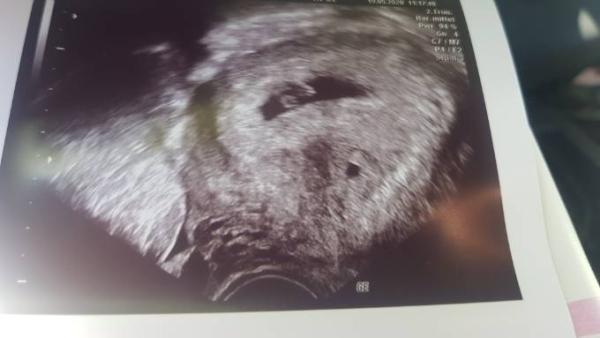

Ich hatte heute meinen Termin, bin 6+3/4. Das Kleine ist ein Eckenhocker, ca 6mm groß und das Herz schlägt eindeutig kräftig Freue mich sehr. Ich hoffe, dass ich unser 2. Wunder im Januar gesund und munter zur Welt bringen darf

Foto vergessen